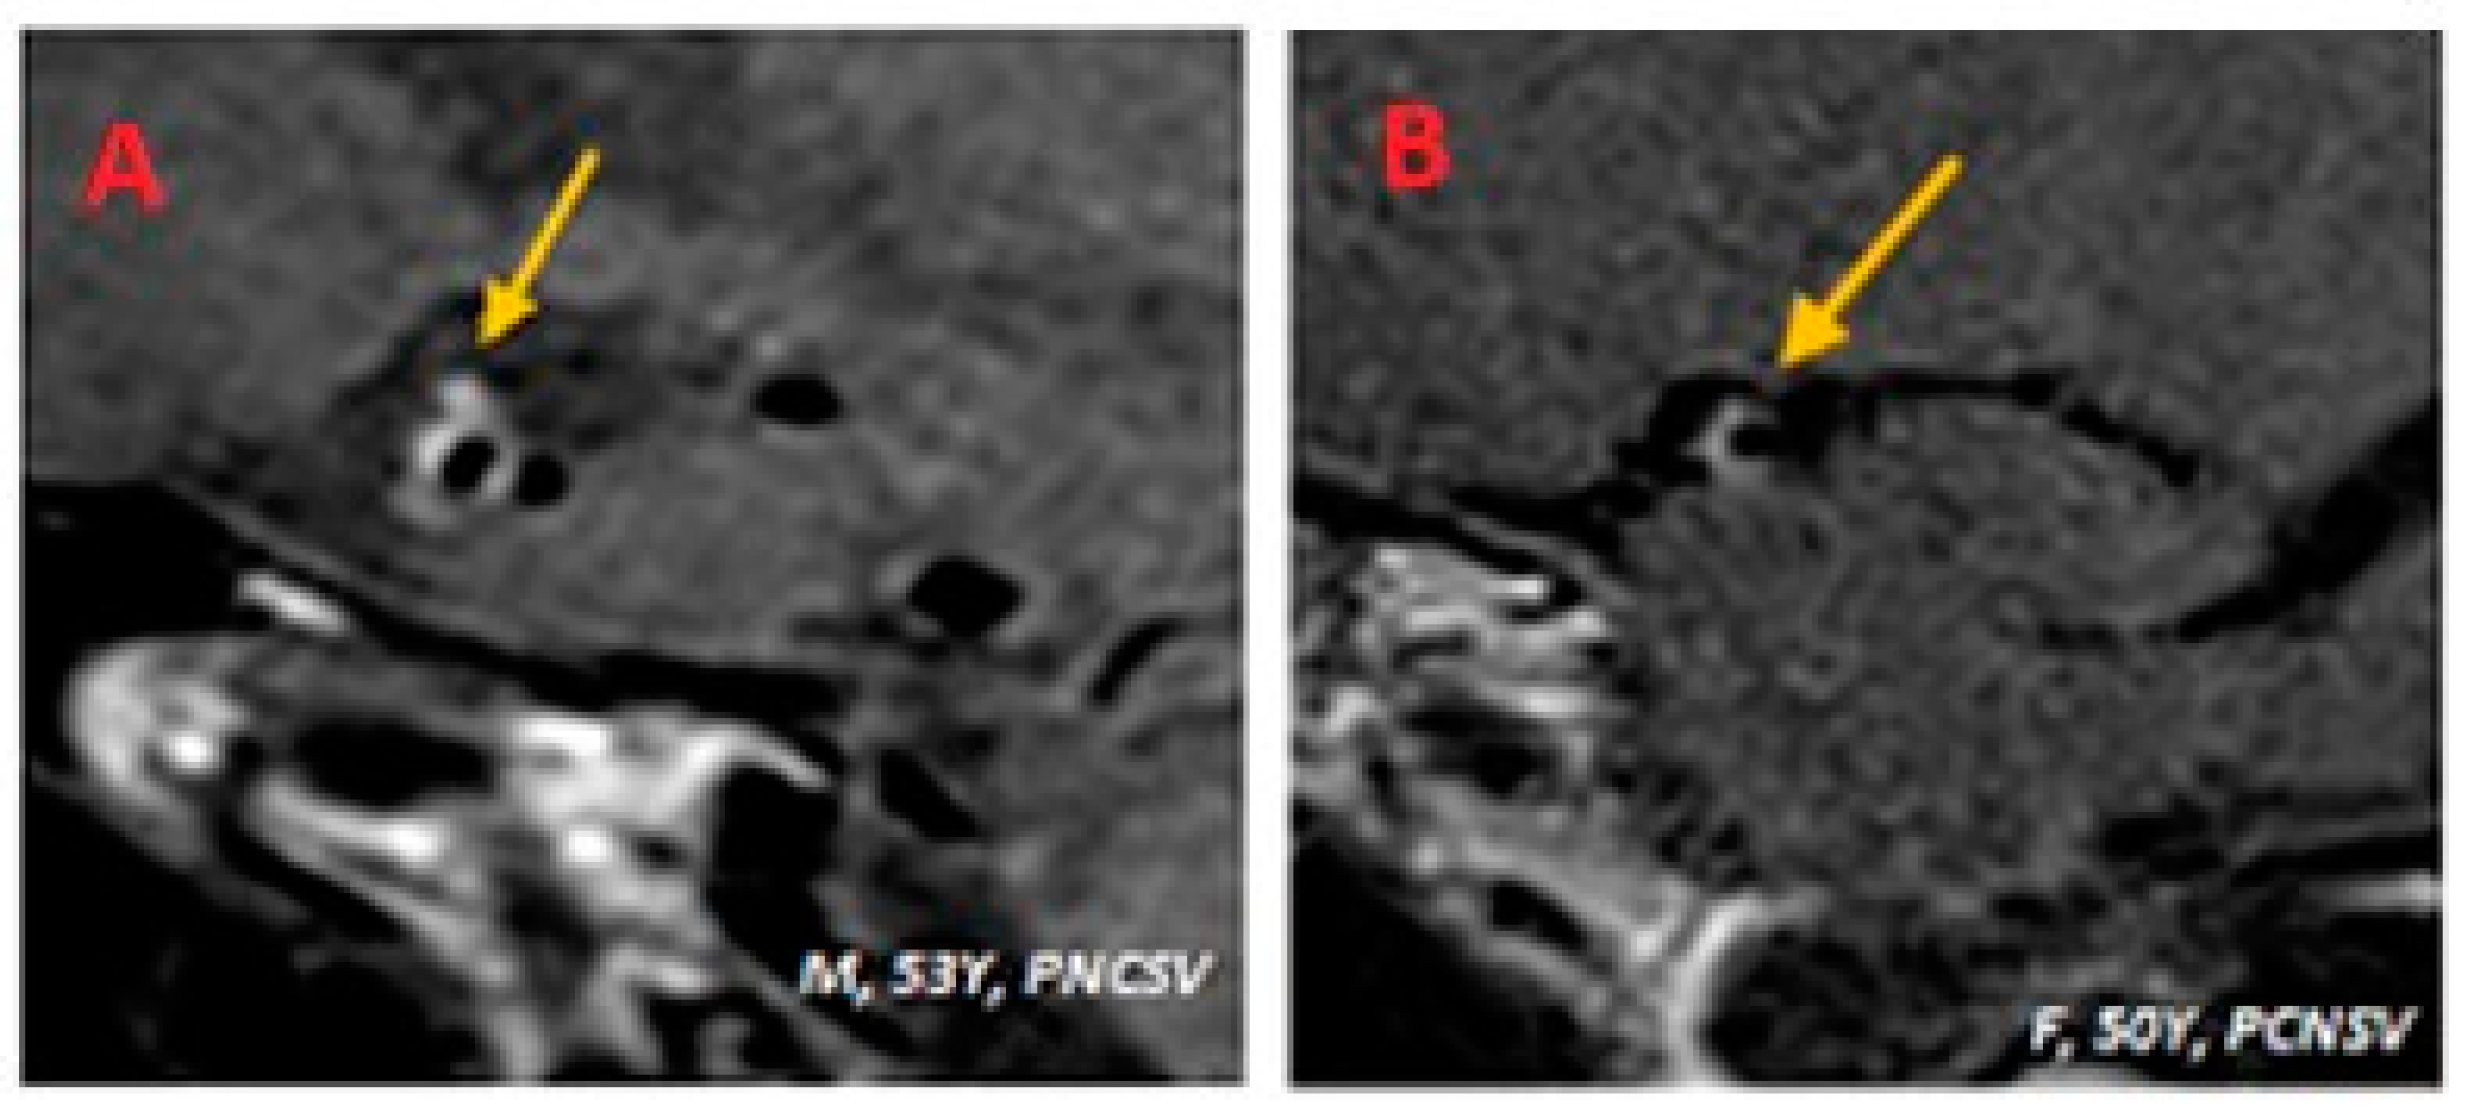

| 53Y M | Episode suggestive of stroke | Non-significative positive | Positive ENA+, anti-SSA RO52 | Negative | Negative | PCNSV |

| 53Y, M | 1 | Present | Present | Fight corona radiata | ICA | ACOP | Present | Supratentorial |

| 49y, M | Headache, hearing disorders | Positive (inflammatory pattern + T. Pallidum positivity) proteins 82 (nv < 50), WBC 73 (nv < 5), TPHA liquor + 1:640 | Negative | T. Pallidum antibody-positive (TPHA > 1:640, RPR +) | (n/a) | Luetic CNSV |

| 49Y, M | 1 | Present | Present | Multiple subcortical in MCA territories | ICA | MCA (M1) ACA (A1) | Present | Subtentorial |